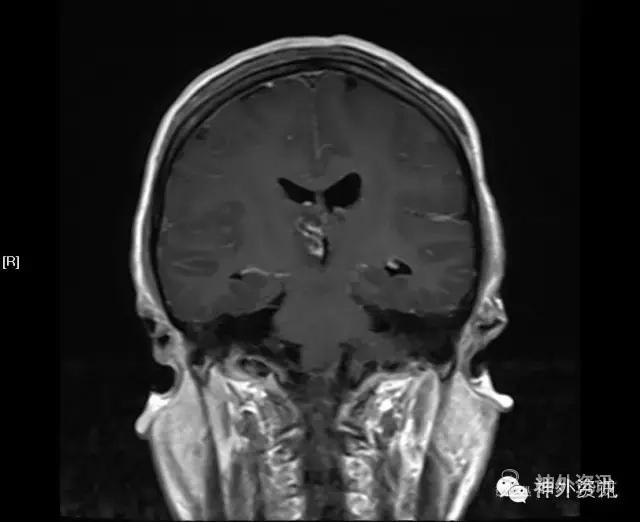

CT头胸部平扫:右丘脑占位,考虑胶质瘤可能,建议进一步检查。左侧基底节区腔梗右下肺感染;左肺上叶舌段异常改变,考虑为畸形血管可能,必要时增强检查两侧胸腔少量积液。

MRI:右侧丘脑占位,考虑胶质瘤可能性大(Ⅲ-Ⅳ级),病灶累及中脑右侧大脑脚,轻度脑积水;不除外转移瘤可能,请结合相关病史及检查。

初步诊断:丘脑占位,胶质瘤可能。

影像学检查: